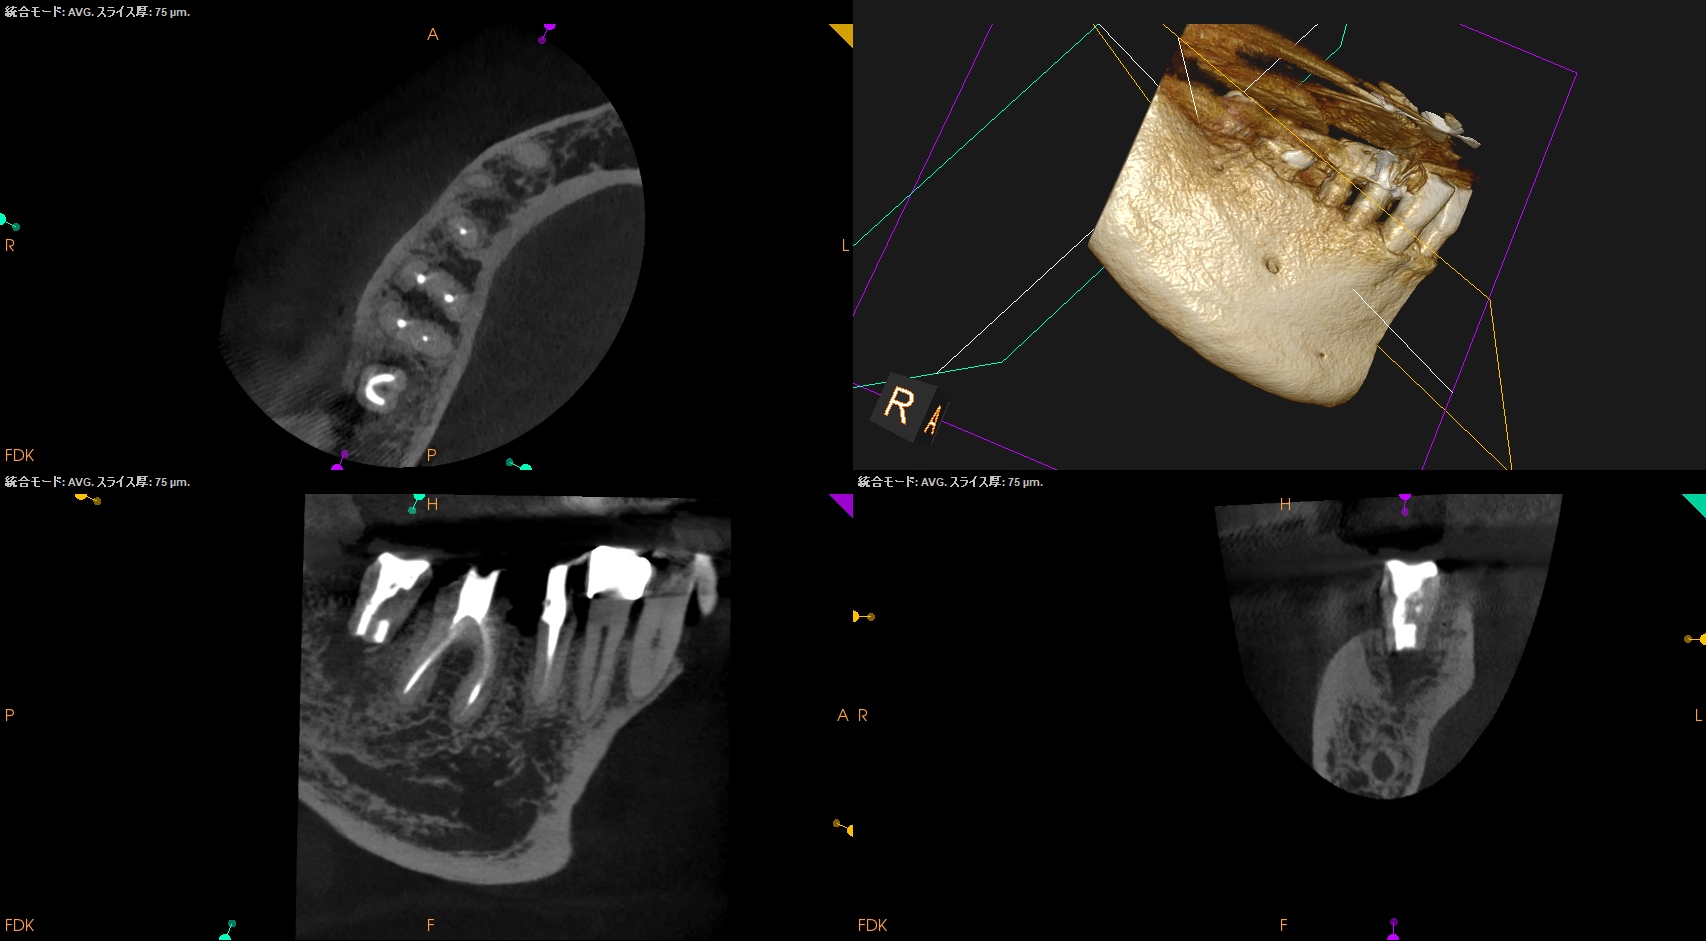

#31 Intentional Replantation 7M recall(2025.12.23)

術前の腫脹、頬側のMBの4mm, Bの6mmの歯周ポケット、歯牙の軽度動揺、咬合痛・圧痛は消失した。

初診時と比較した。

劇的に状態は改善した。

最終補綴もOKである。

次回はさらに半年の1年後の予後を報告したい。